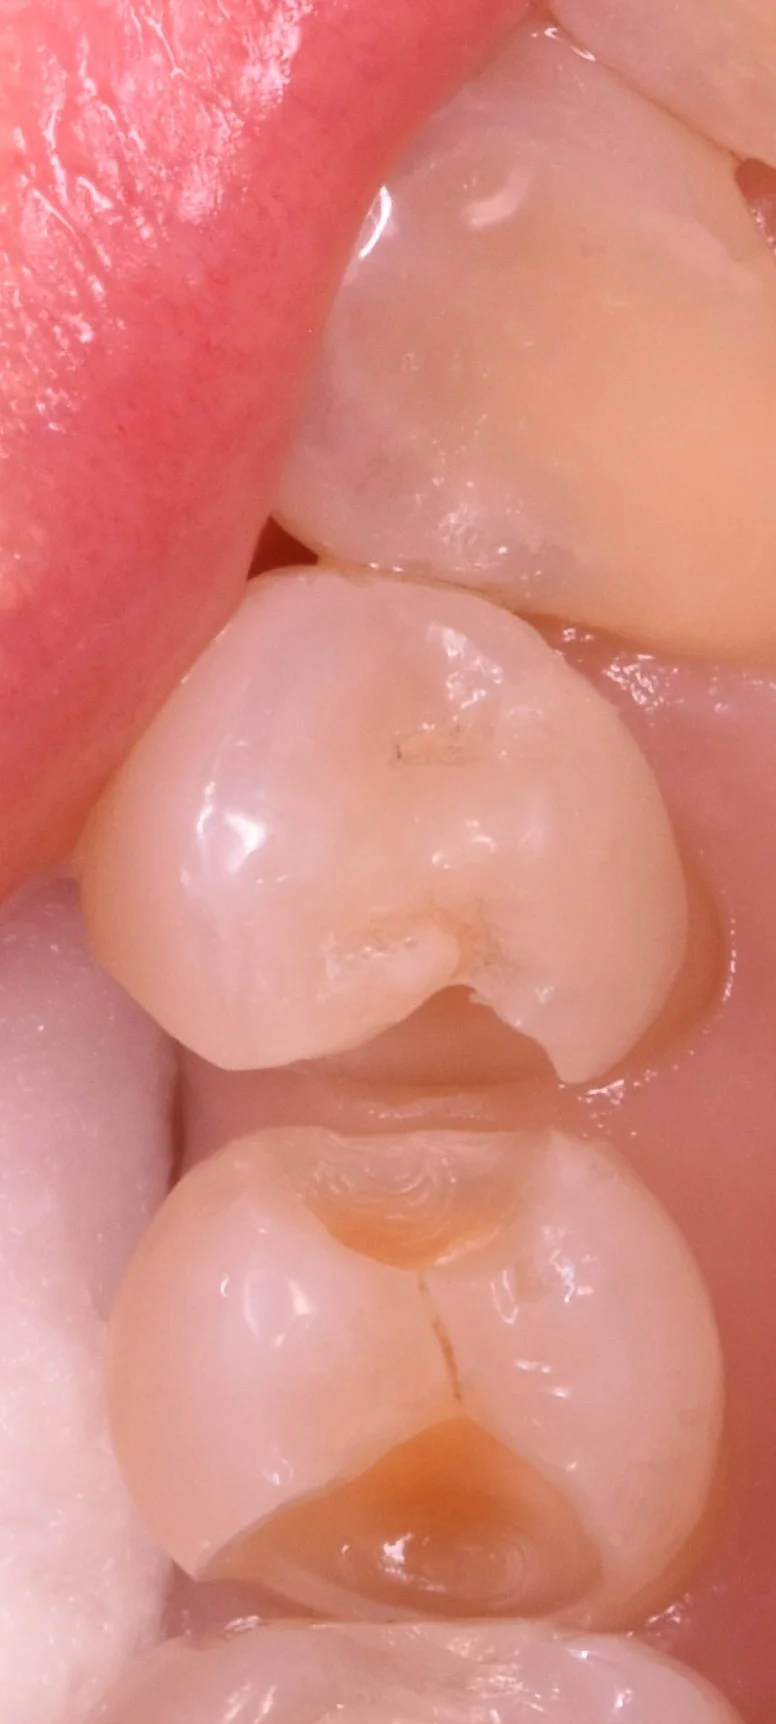

削って軽く虫歯が見やすくなった状態がこちらです。

奥歯の歯並びが悪くなってしまっている所の治療|坂寄歯科医院(取手市藤代) - 画像2

内面が茶色くなってしまっているのが分かるかと思います。

そして取りきったのがこちらです。

奥歯の歯並びが悪くなってしまっている所の治療|坂寄歯科医院(取手市藤代) - 画像3

随分と綺麗に歯の色が出たかと思います。